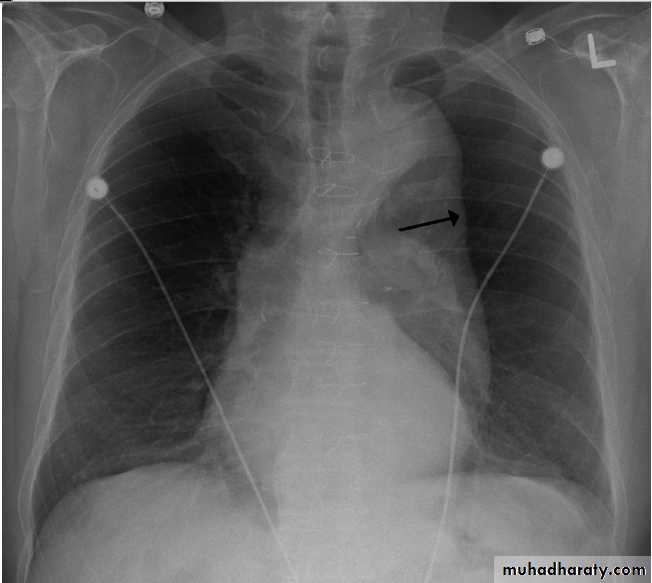

Thymoma.

A chest x-ray (A) reveals an unusual contour over the left hilum (arrows). That the hilum is not obscured (no silhouette sign) indicates that the mass must either be in front of or behind the hilum. A computed tomography scan (B) reveals a soft tissue mass (arrow) just to the left of the aorta. This is the most common location of a thymoma.